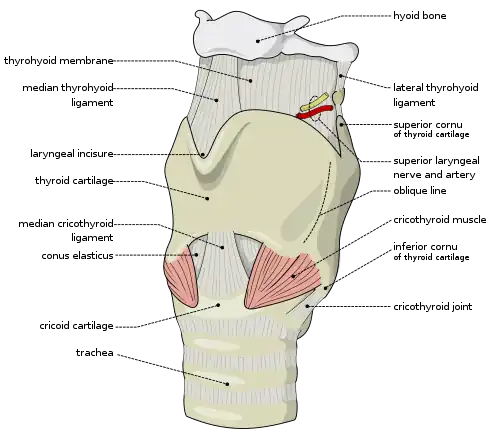

Cricothyrotomy

A cricothyrotomy is an incision made through the skin and cricothyroid membrane to establish a patent airway during certain life-threatening situations, such as airway obstruction by a foreign body, angioedema, or massive facial trauma.[54] A cricothyrotomy is nearly always performed as a last resort in cases where orotracheal and nasotracheal intubation are impossible or contraindicated. Cricothyrotomy is easier and quicker to perform than tracheotomy, does not require manipulation of the cervical spine and is associated with fewer complications.[55]

The easiest method to perform this technique is the needle cricothyrotomy (also referred to as a percutaneous dilational cricothyrotomy), in which a large-bore (12–14 gauge) intravenous catheter is used to puncture the cricothyroid membrane.[56] Oxygen can then be administered through this catheter via jet insufflation. However, while needle cricothyrotomy may be life-saving in extreme circumstances, this technique is only intended to be a temporizing measure until a definitive airway can be established.[57] While needle cricothyrotomy can provide adequate oxygenation, the small diameter of the cricothyrotomy catheter is insufficient for elimination of carbon dioxide (ventilation). After one hour of apneic oxygenation through a needle cricothyrotomy, one can expect a PaCO2 of greater than 250 mm Hg and an arterial pH of less than 6.72, despite an oxygen saturation of 98% or greater.[58] A more definitive airway can be established by performing a surgical cricothyrotomy, in which a 5 to 6 mm (0.20 to 0.24 in) endotracheal tube or tracheostomy tube can be inserted through a larger incision.[59]

Several manufacturers market prepackaged cricothyrotomy kits, which enable one to use either a wire-guided percutaneous dilational (Seldinger) technique, or the classic surgical technique to insert a polyvinylchloride catheter through the cricothyroid membrane. The kits may be stocked in hospital emergency departments and operating suites, as well as ambulances and other selected pre-hospital settings.[60]

Tracheotomy

1 - Vocal folds

2 - Thyroid cartilage

3 - Cricoid cartilage

4 - Tracheal rings

5 - Balloon cuff

Tracheotomy consists of making an incision on the front of the neck and opening a direct airway through an incision in the trachea. The resulting opening can serve independently as an airway or as a site for a tracheostomy tube to be inserted; this tube allows a person to breathe without the use of his nose or mouth. The opening may be made by a scalpel or a needle (referred to as surgical[59] and percutaneous[61] techniques respectively) and both techniques are widely used in current practice. In order to limit the risk of damage to the recurrent laryngeal nerves (the nerves that control the voice box), the tracheotomy is performed as high in the trachea as possible. If only one of these nerves is damaged, the patient's voice may be impaired (dysphonia); if both of the nerves are damaged, the patient will be unable to speak (aphonia). In the acute setting, indications for tracheotomy are similar to those for cricothyrotomy. In the chronic setting, indications for tracheotomy include the need for long-term mechanical ventilation and removal of tracheal secretions (e.g., comatose patients, or extensive surgery involving the head and neck).[62][63]